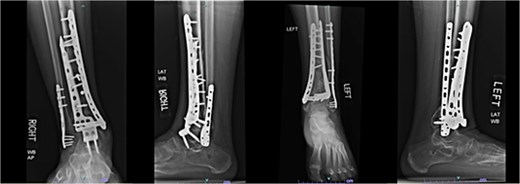

Despite the patient’s noncompliance, he went on to heal uneventfully for the next 2 years until the patient fell from a height of 15 feet, resulting in a left bicondylar tibial plateau fracture and fracture of the left tibial shaft. These injuries required ORIF of his left tibia. Despite the new injury, the hardware from the pilon fractures was in proper alignment (Fig. 4).

Two-year follow-up AP and lateral radiographs of both ankles in patient 2 showing maintained alignment and hardware position.